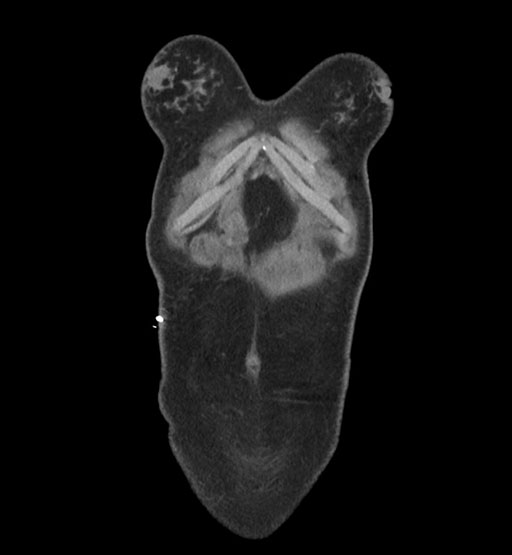

MRI T1

MRI T2

Imaging analysis

Based on initial findings, which issue(s) would you be most concerned about?